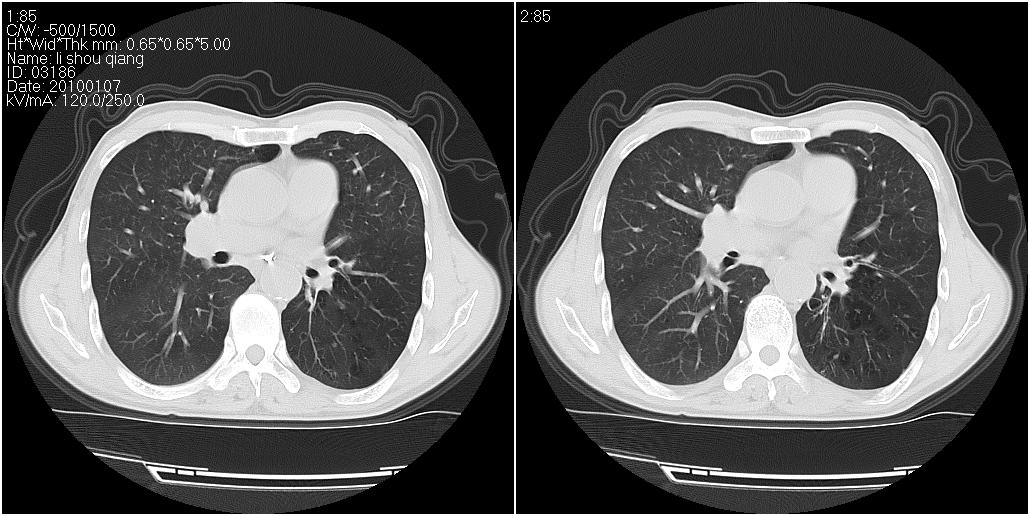

标题: CT24038:男性,58岁。主因咳嗽带血性CT检查。 [打印本页]

标题: CT24038:男性,58岁。主因咳嗽带血性CT检查。

右肺中叶外侧段见一不规则的软组织肿块,边缘可见毛刺,并见厚壁空洞,与胸膜分界欠清。另左下肺见多个小囊状扩张区

1、右肺中叶周围型肺癌并空洞形成。

2、左肺下叶支扩可能性大。

右肺中叶外侧段可见团块影,外形不规则,内见空泡征。左下肺见蜂窝状低密度透亮影,部分层面主动脉旁瘤样突出。考虑右肺中叶外围型肺癌可能性大,左下肺支气管扩张,主动脉弓瘤样突出。

1)考虑右肺中叶周围型肺癌并癌性空洞形成。2)左肺下叶支气管扩张可能性大。

1、右肺中叶周围型肺癌(内空泡)。

2、左肺下叶支扩,不除外合并肺囊肿。